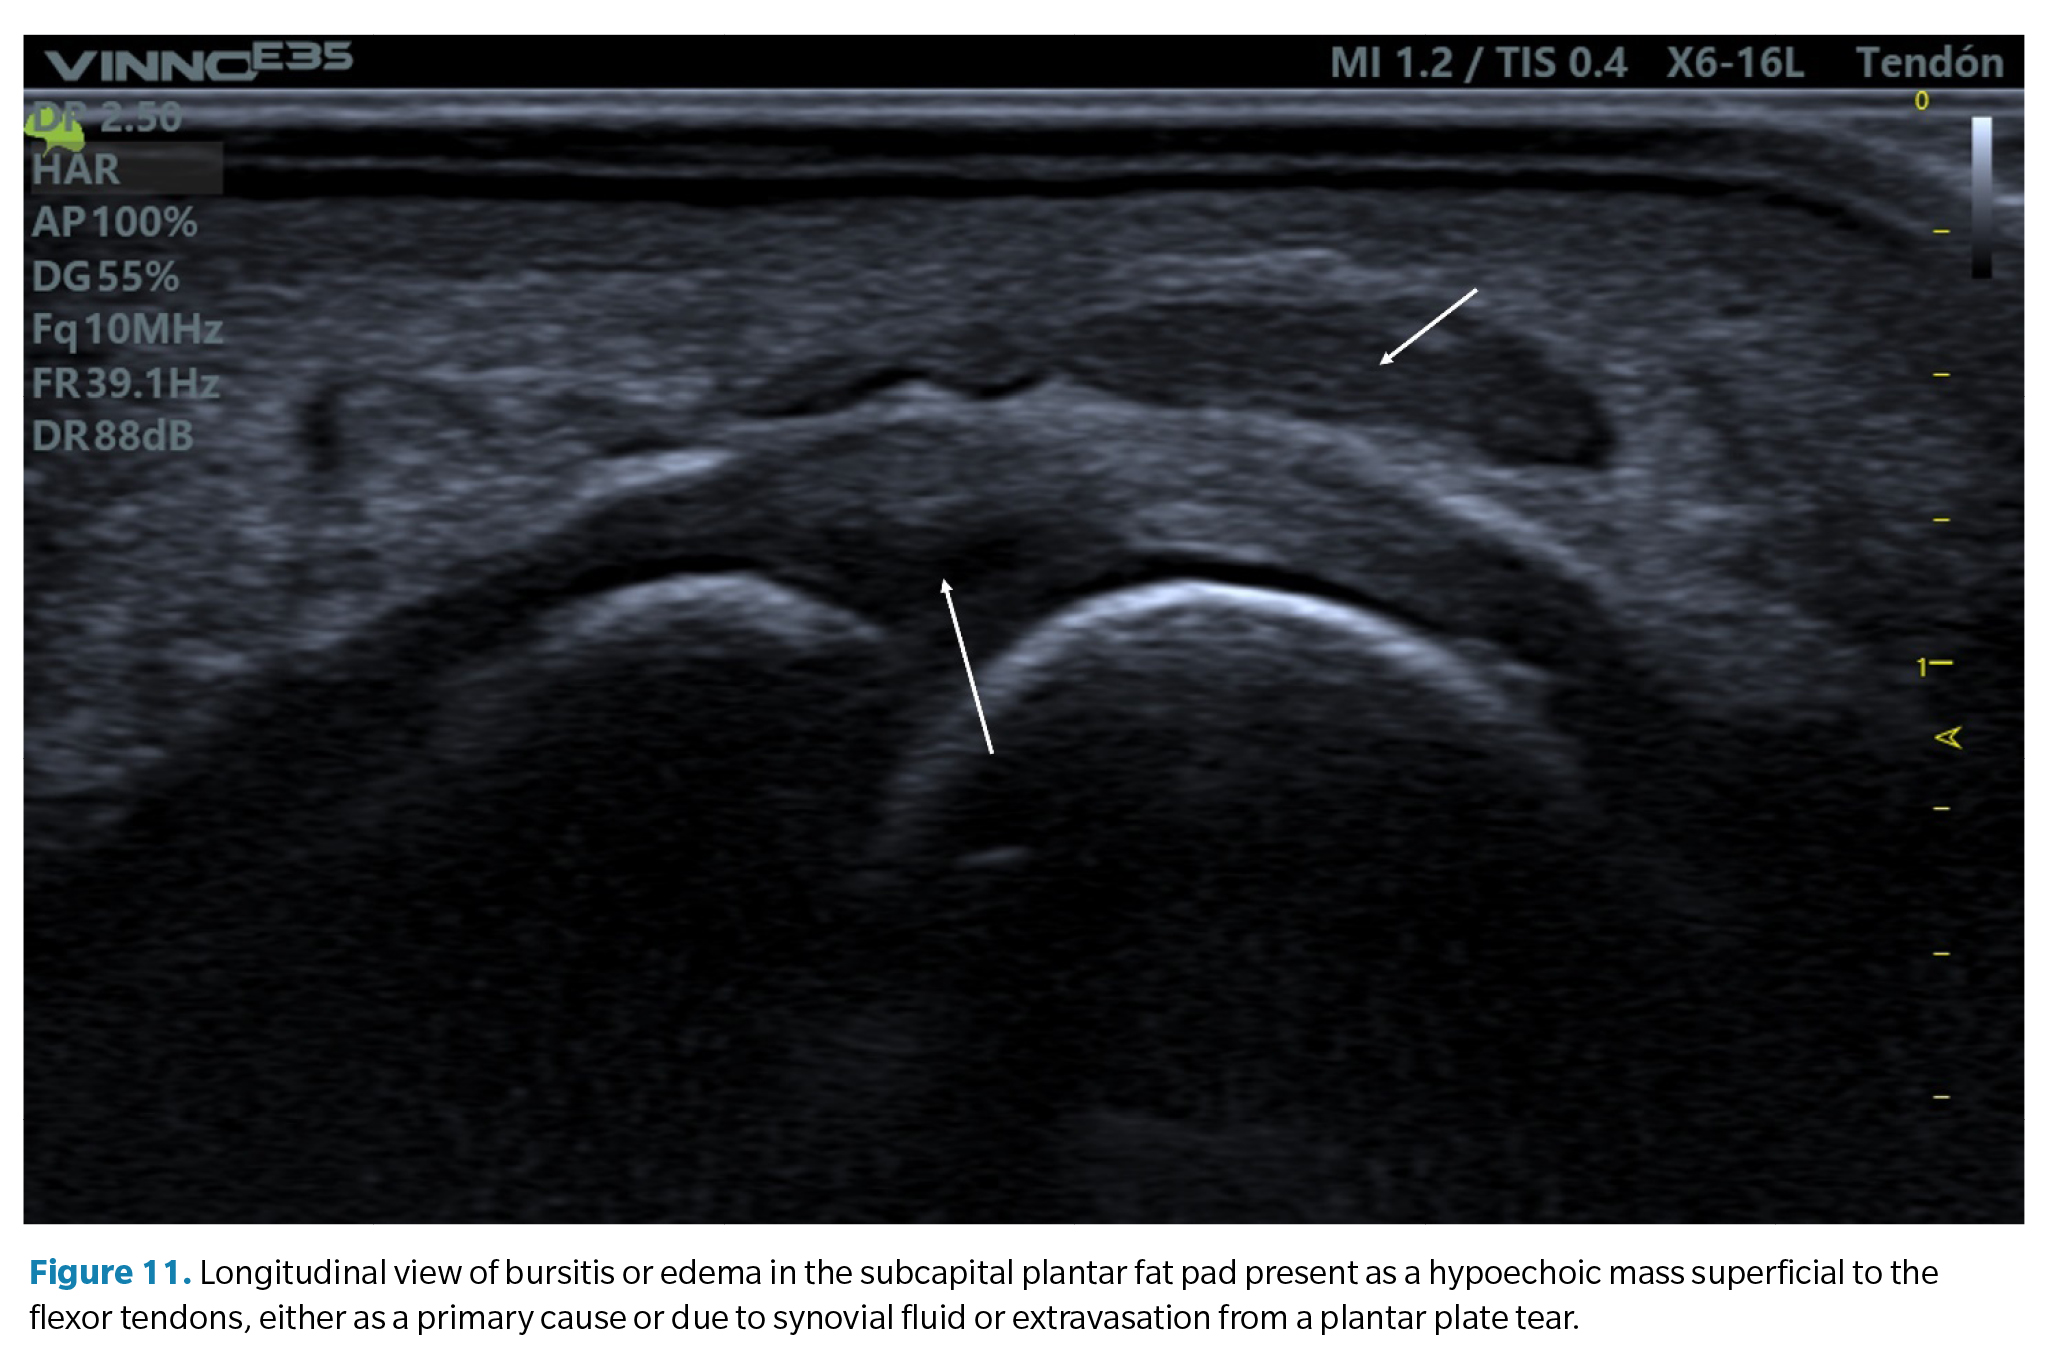

1. Plantar or dorsal joint fluid (synovitis). Synovial effusion. Since the plantar plate forms the plantar closure of the joint capsule, tears in the plate can lead to a significant increase in synovial fluid, which manifests as a detectable synovial effusion both dorsally and plantarly. In some cases, this fluid can leak into the flexor tendons, creating a hypoechoic halo around them resembling the characteristic image of tenosynovitis with distension of the tendon sheath (Figure 10).

2. Bursitis of the plantar fat pad. In relation to the previous finding, some cases of plantar plate tears may also be accompanied by a hypoechoic infiltrate in the adjacent plantar fat pad. This may be a primary defect due to excessive compression of the fat (compression which is also part of the compressive injury etiology of the plate) or the result of a synovial fluid infiltrate due to capsular rupture extravasation as previously mentioned. It is common in these cases to detect a positive <